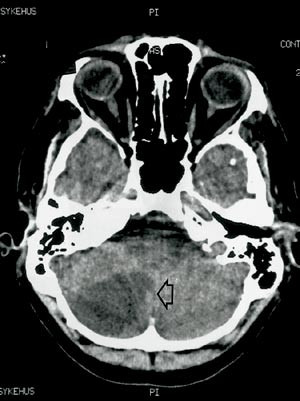

Han ble akutt syk med hodepine, svimmelhet, kvalme og brekninger. Symptomene gikk helt tilbake i løpet av få timer, med unntak av hodepinen, som likevel avtok etter hvert. Ved innleggelse i lokalsykehus samme kveld fant man ingen nevrologiske utfall. Cerebral CT viste imidlertid utvikling av et stort høyresidig lillehjerneinfarkt (fig 1). Det tilkom ikke trykksymptomer. Han ble overflyttet nevrologisk avdeling for videre utredning.

Ved klinisk undersøkelse var det normal nevrologisk status, inklusive skjerpet Rombergs prøve, til tross for at store deler av høyre lillehjernehemisfære var infarsert. Det var ikke kliniske holdepunkter for dyp venetrombose. Blodprøver viste Hb 11,8 g/100 ml, trombocytter 231 · 10⁹/l, SR 7 mm, INR 1,3. Aktiviteten for protein C, S og antitrombin III viste normale verdier, og det ble ikke påvist APC-resistens eller antifosfolipidantistoffer.